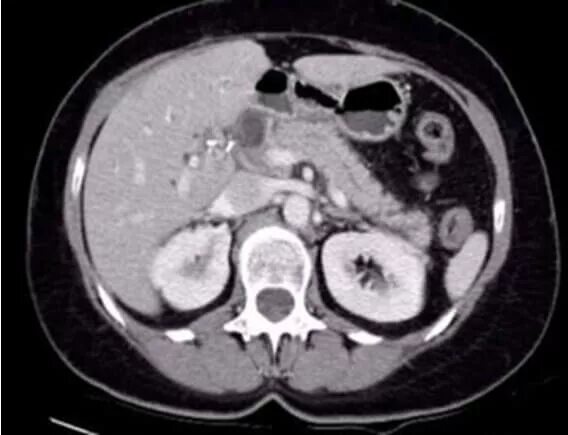

Диффузные изменения печени кт